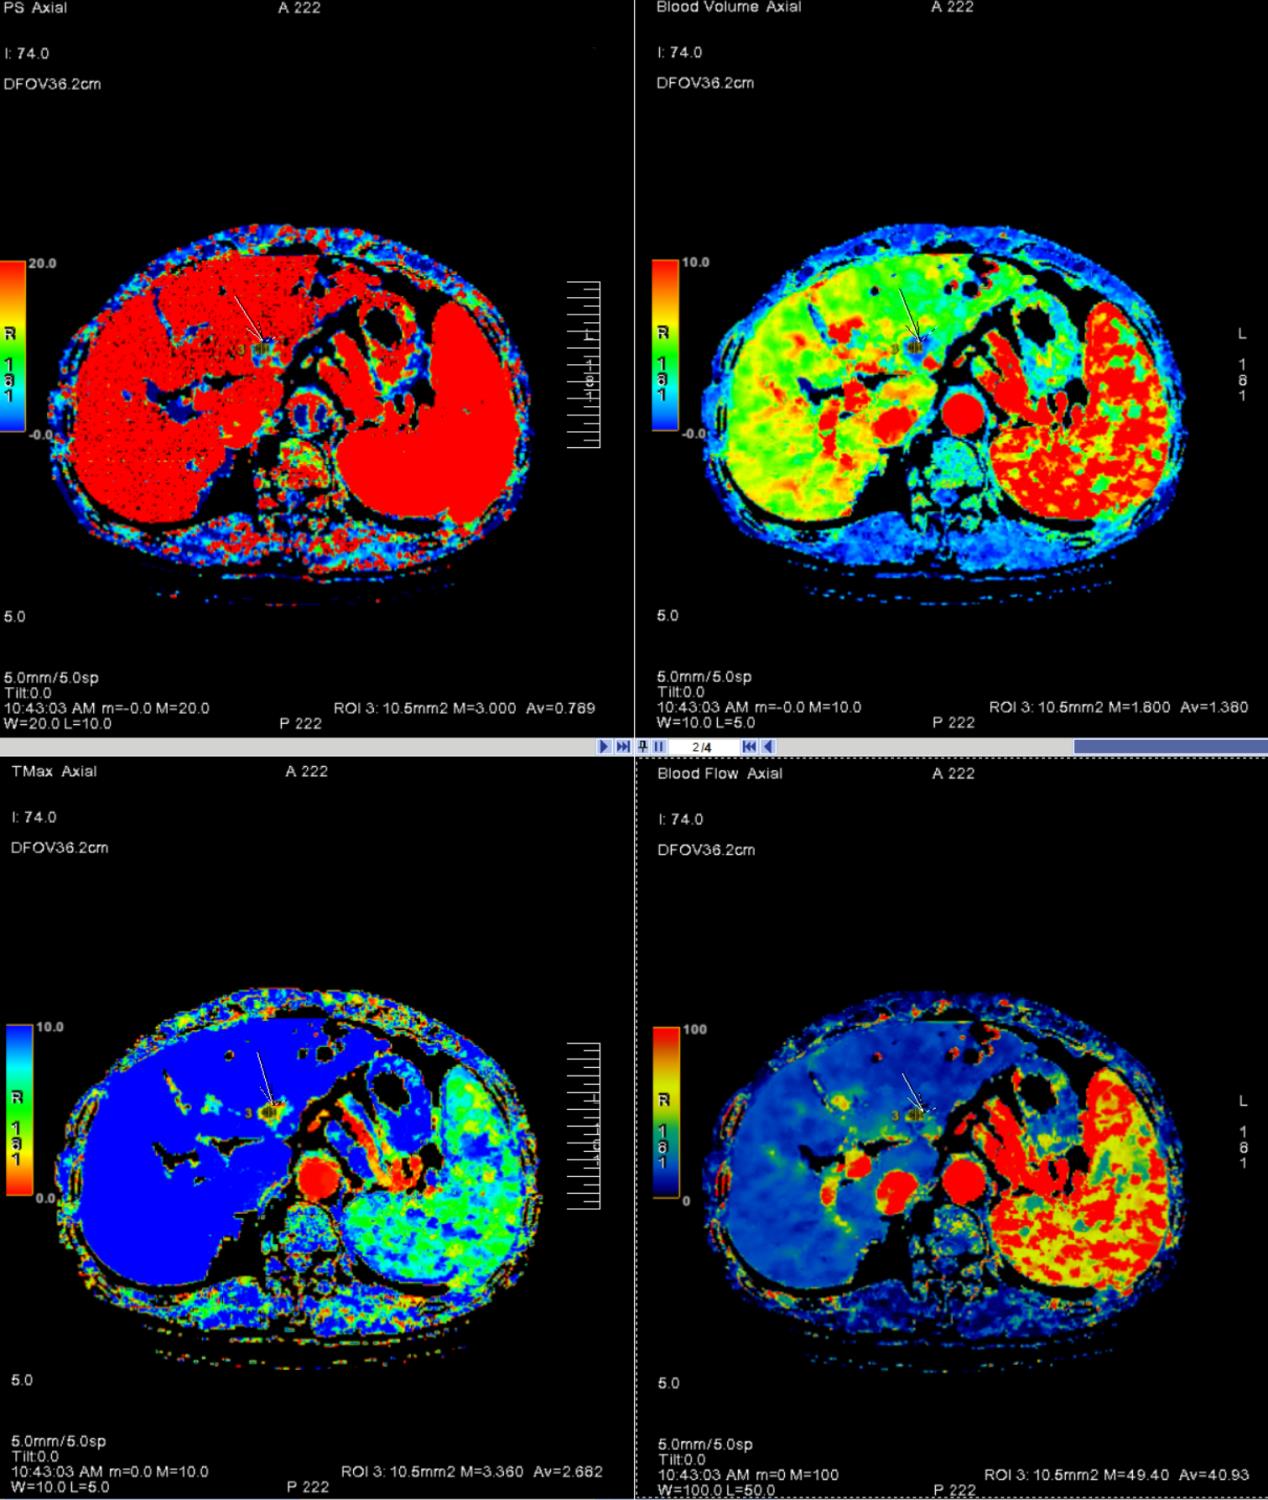

Application of CT perfusion parameters and serum CEA/AFP in monitoring post-TACE recurrence in primary hepatocellular carcinoma

Objective To investigate the application of CT perfusion (CTP) parameters, carcinoembryonic antigen (CEA), and alpha-fetoprotein (AFP) in monitoring recurrence after transcatheter arterial chemoembolization (TACE) in patients with primary hepatocellular carcinoma (HCC). Methods A retrospective analysis was conducted on 203 HCC patients who underwent TACE at the hospital from September 2022 to September 2023. CTP parameters [blood flow (BF), blood volume (BV), hepatic arterial perfusion index (HAI), portal venous perfusion (PVP)], CEA, and AFP levels were measured before and one month after TACE. Patients were followed up for one year and divided into recurrence and non-recurrence groups based on tumor status. Differences in BF, BV, HAI, PVP, CEA, and AFP levels between the two groups were compared. Receiver operating characteristic (ROC) curves were plotted to evaluate the predictive value of these indicators for post-TACE recurrence, and logistic regression was used to analyze influencing factors. Results Compared with pre-TACE levels, BF, BV, HAI, CEA, and AFP decreased one month after TACE, while PVP increased (P < 0.05). Among the 203 patients, 75 (36.95%) experienced recurrence, while 128 (63.05%) remained recurrence-free. Compared with the non-recurrence group, the recurrence group exhibited higher BF, BV, HAI, CEA, and AFP levels and lower PVP (P < 0.05). The AUC values for BF, BV, HAI, PVP, CEA, and AFP in predicting recurrence were 0.771, 0.787, 0.787, 0.735, 0.771, and 0.795, respectively. The combined detection of these indicators yielded an AUC of 0.968 (P < 0.05). Logistic regression identified BF, BV, HAI, PVP, CEA, and AFP as independent risk factors for post-TACE recurrence (P < 0.05). Conclusion CTP combined with serum tumor markers can effectively predict early recurrence in HCC patients after TACE.